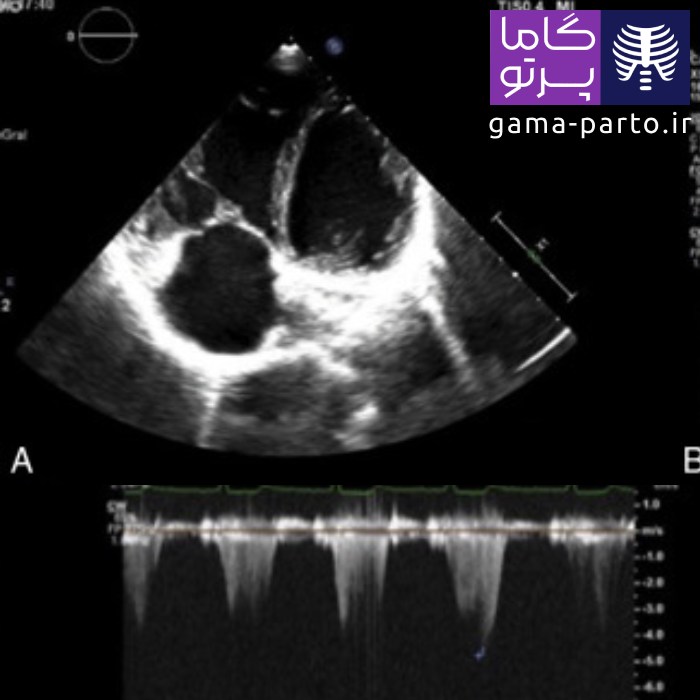

اکوکاردیوگرافی قفسهای (ترانس توراسیک)

یکی از رایجترین و استانداردترین روشها برای ارزیابی قلب، اکوکاردیوگرافی ترانس توراسیک یا Transthoracic Echocardiography است. این روش غیرتهاجمی، کاملاً بدون درد بوده و مانند تصویربرداری با اشعه ایکس عمل میکند.

البته در این فرایند از امواج اولتراسوند استفاده میشود، نه اشعه. در این نوع اکو، دستگاه مخصوصی امواج صوتی را به سمت قلب میفرستد و بازتاب این امواج تصاویری از ساختار داخلی قلب ایجاد میکند که متخصص با تحلیل آنها وضعیت سلامت قلب را تشخیص میدهد.